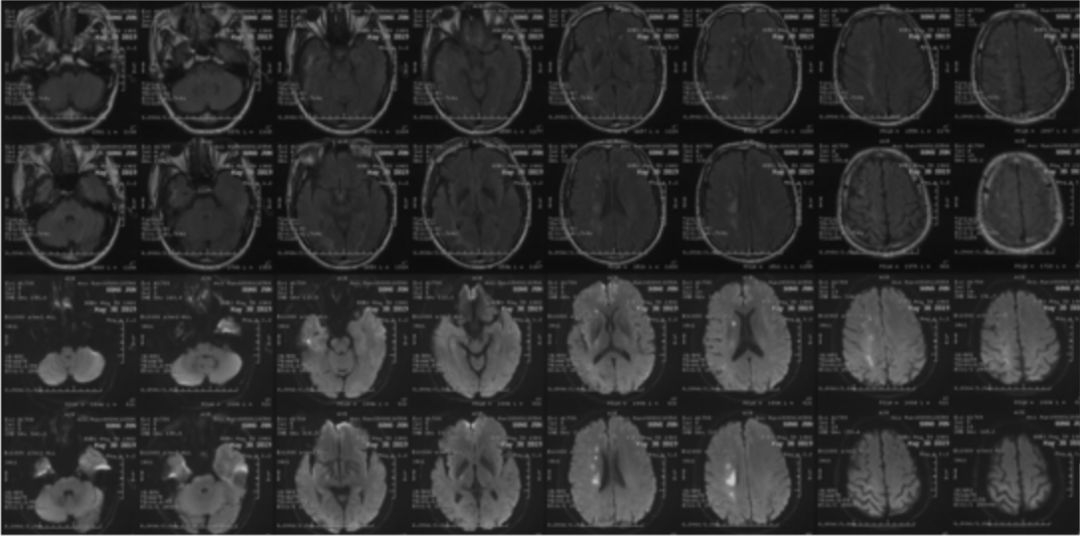

2019-07-05北京军颐中医医院高分辨核磁:

1.右侧颈内动脉夹层形成并血栓形成、管腔闭塞。

2.左侧颈内动脉眼段管腔中度狭窄,局部夹层不排除。

3.右侧大脑中动脉起始部管壁增厚,管腔重度狭窄(图3)。

图3